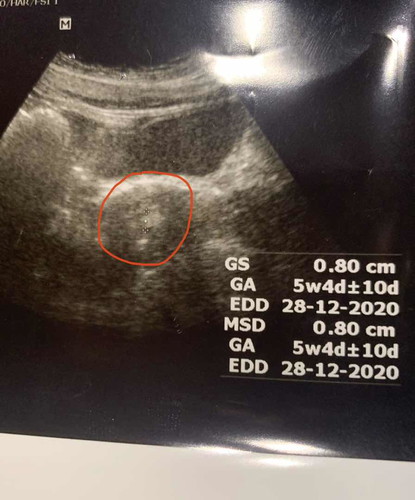

วันนี้ครบ2อาทิตย์จากครั้งที่แล้วที่หมอนัด ซาวด์ดูผ่านหน้าท้องนะคะ หมอแจ้งว่าท้องเห็นถุงตั้งครรภ์ +ด้วยประจำเดือนยังไม่มาพอซาวด์เสร็จ หมอให้ไปตรวจปัสสาวะ แต่ผลตรวจขึ้นแค่1ขีด แล้วหมอก็บอกว่า ถุงที่เห็นอาจเป็นถุงของประจำเดือนที่กำลังจะมา ให้รอต่ออีก2อาทิตย์ ถ้าประจำเดือนมาก็จบไม่ท้อง ทิ้งท้ายแล้วถุงที่เห็นมันถุงอะไร เลยอยากมาถามว่าแบบนี้มีสิทธิ์จะท้องไหมคะ หรือไม่ท้อง